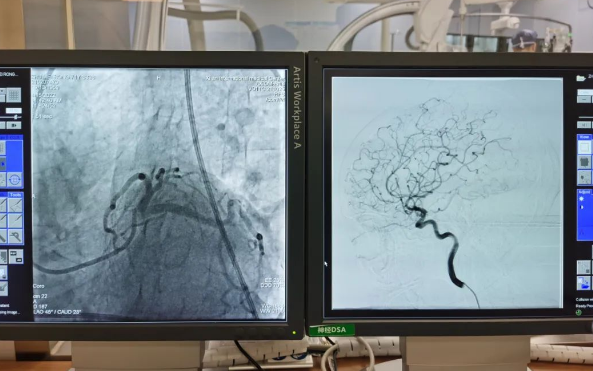

術(shù)前準(zhǔn)備就緒后,心內(nèi)二病區(qū)曾廣偉主任、高釗副主任醫(yī)師、神外科陸丹副主任醫(yī)師共同為患者行腦血管造影術(shù) 冠狀造影術(shù)。術(shù)后,朱奶奶恢復(fù)良好。

陸丹副主任醫(yī)師介紹,由于腦血管疾病和心血管疾病有著共同的病理變化基礎(chǔ)——?jiǎng)用}粥樣硬化,臨床中,兩類疾病交叉存在的情況十分多見。“心腦同治”的模式不僅能讓患者獲得較好治療,還能夠降低患者就醫(yī)的時(shí)間成本和經(jīng)濟(jì)成本。